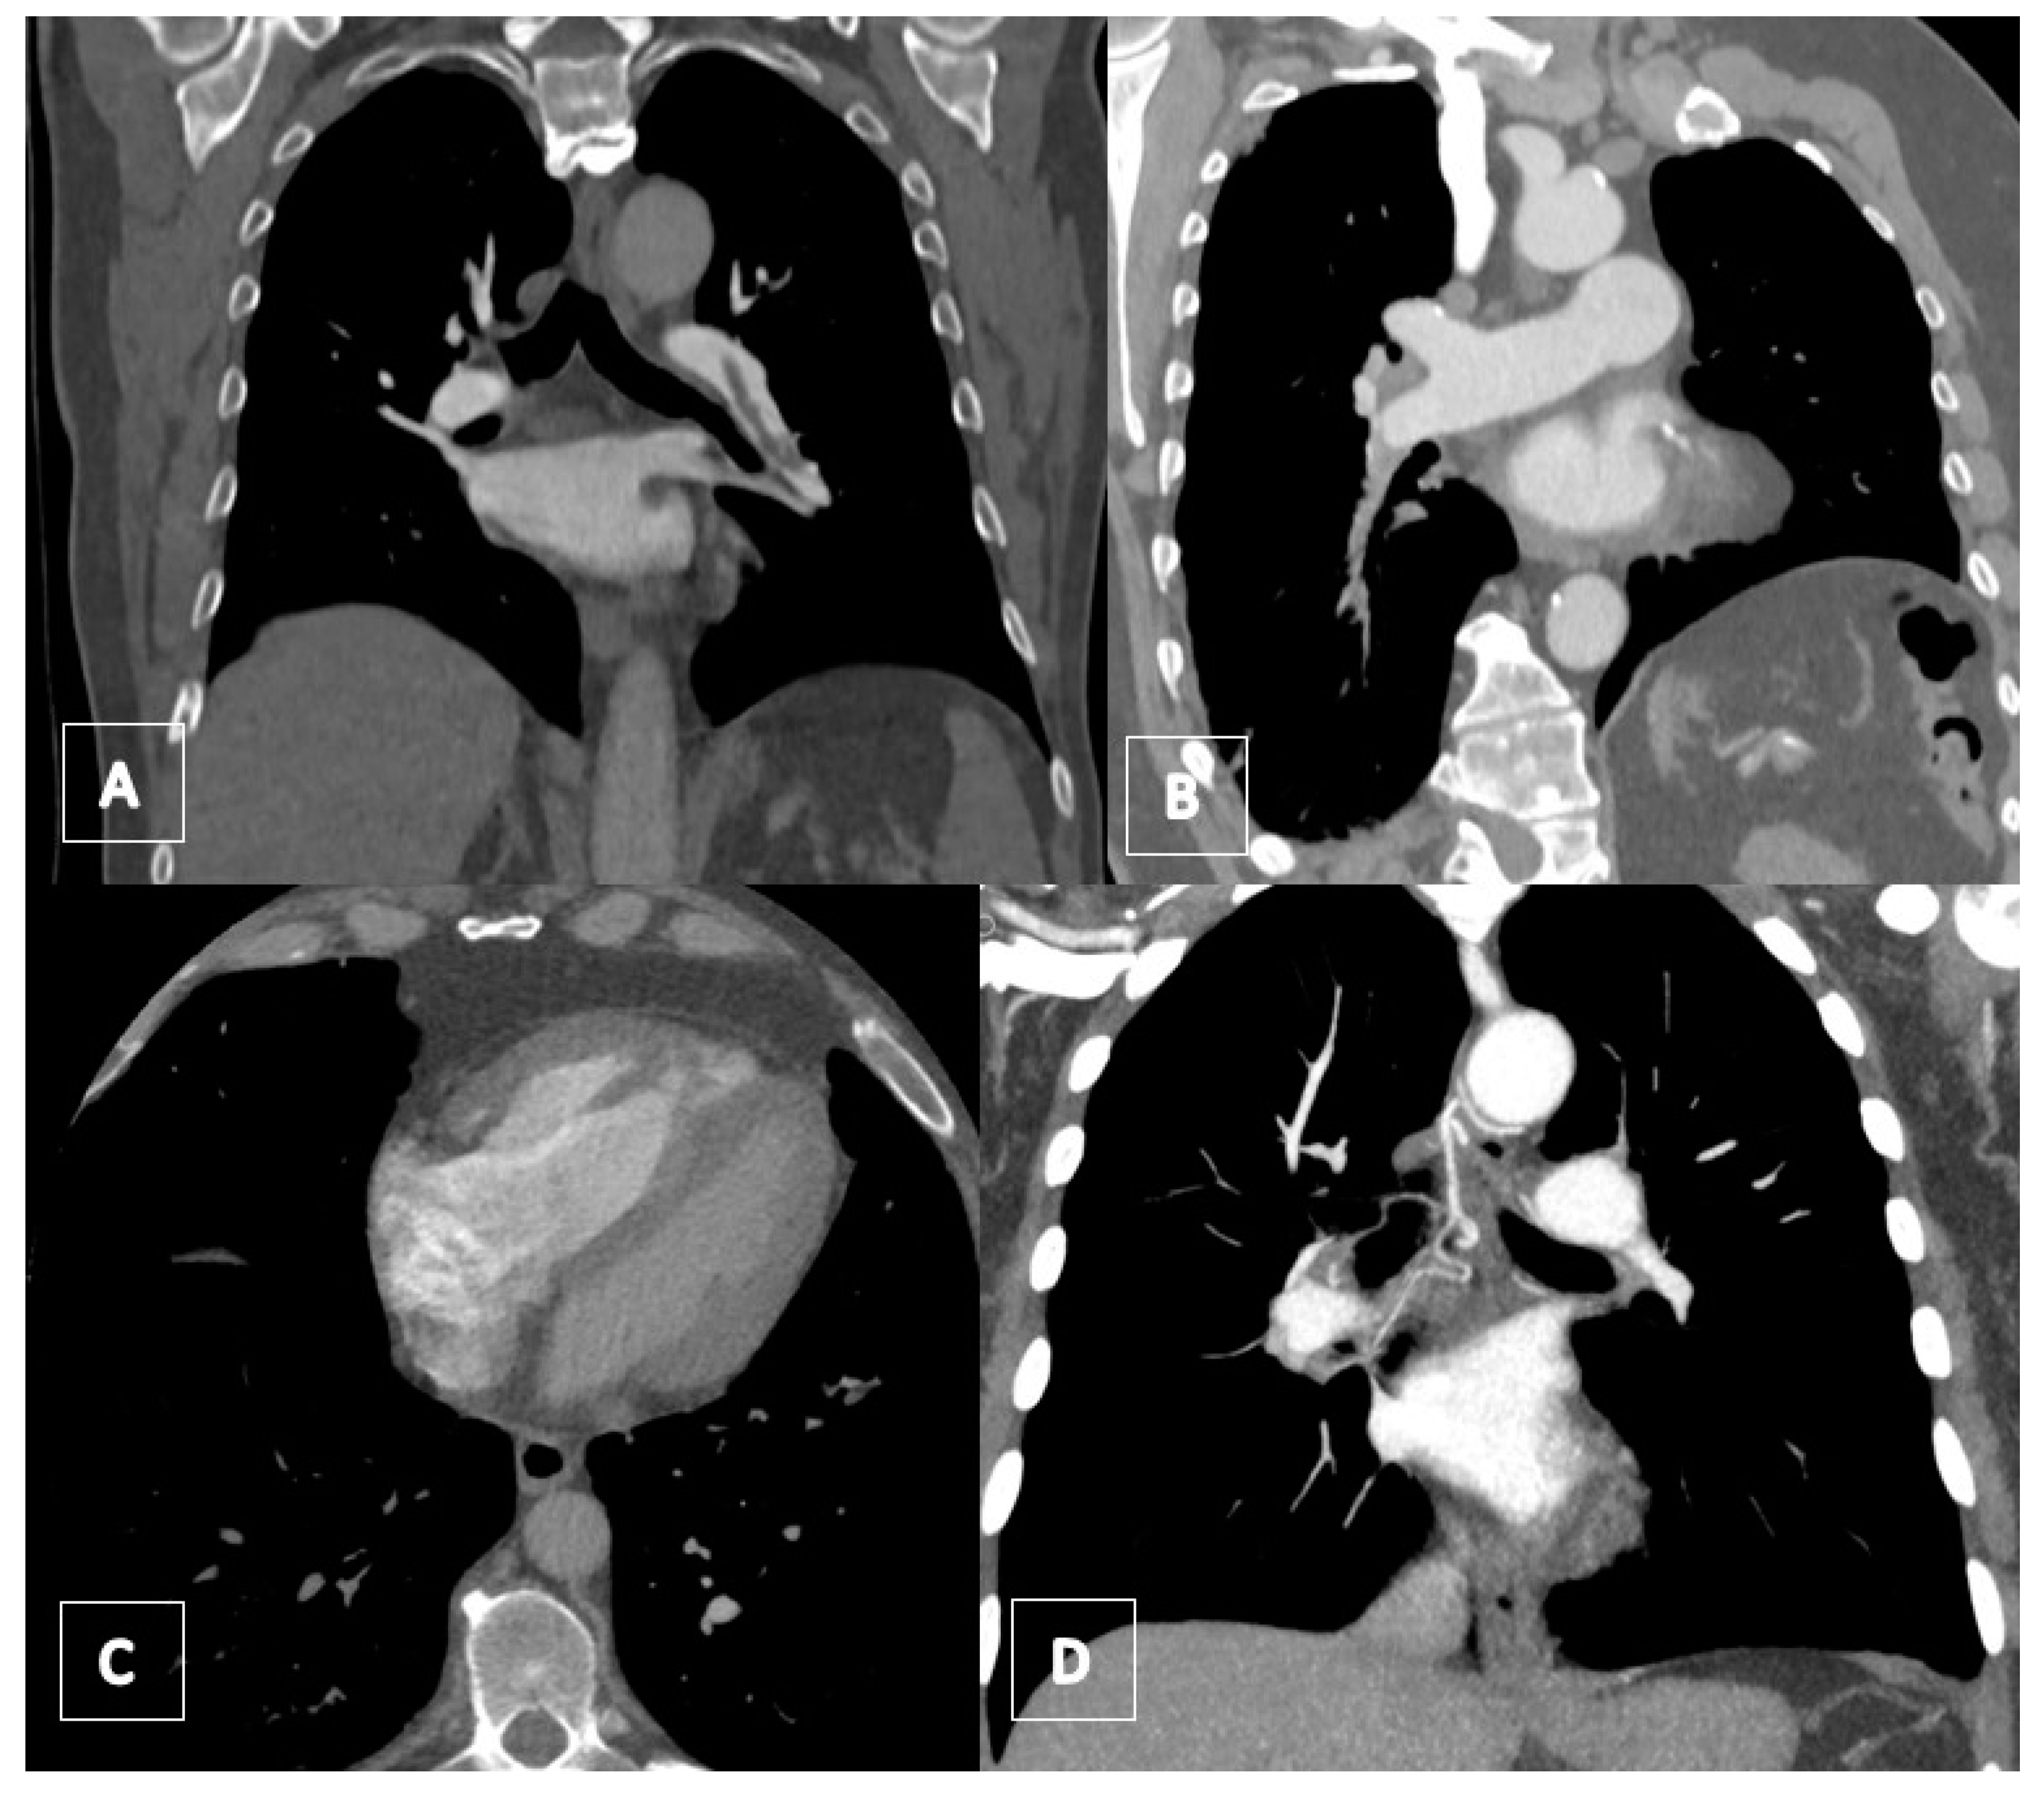

3.3. Imaging

3.4. Computed Tomography Pulmonary Angiography (CTPA)